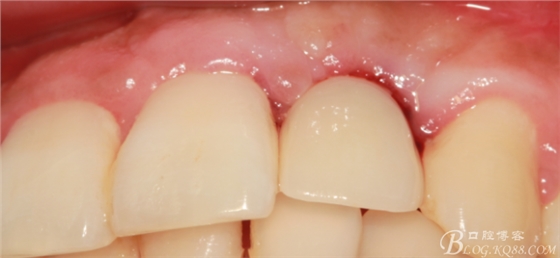

4個(gè)月后,唇側(cè)豐滿度尚可,與鄰牙之間齦乳頭完整。

兩個(gè)月后戴入永久修復(fù)體。

戴入永久修復(fù)體當(dāng)天口內(nèi)照,雖有小瑕疵,但患者很滿意。